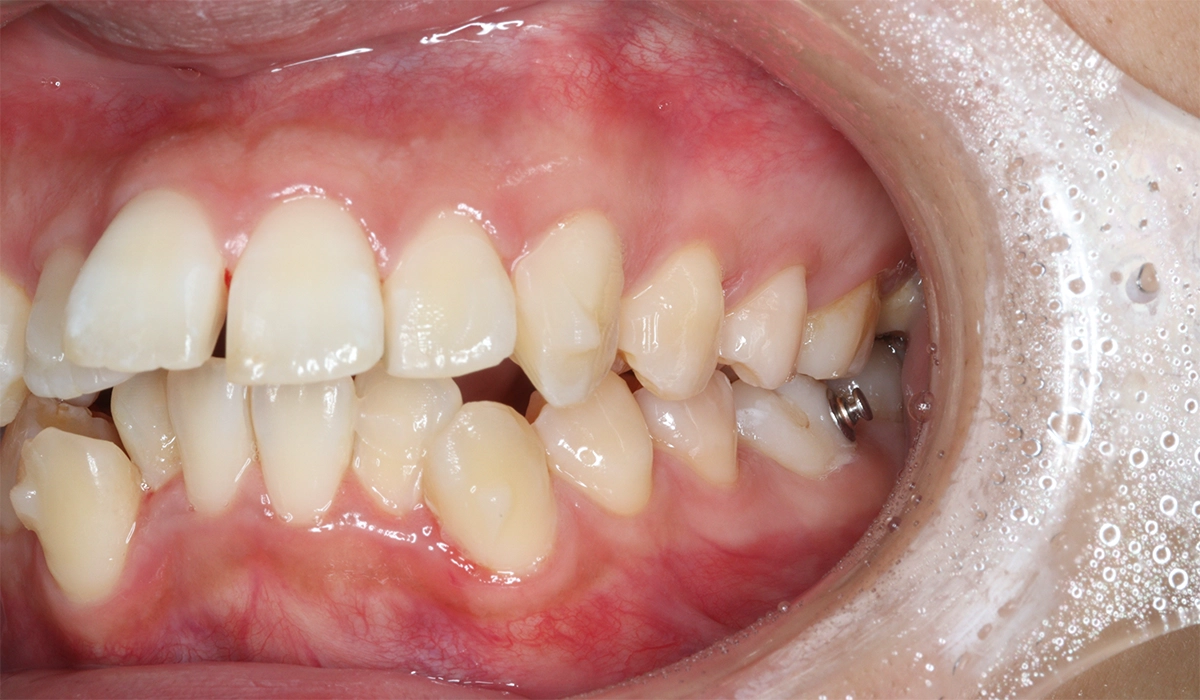

術前:左側

術後:左側